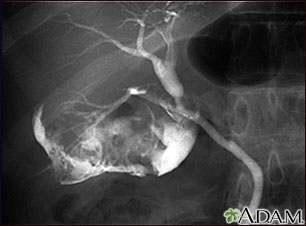

Cholelithiasis can be seen on a cholangiogram. Radio-opaque dye is used to enhance the x-ray. Multiple stones are present in the gallbladder (PTCA).